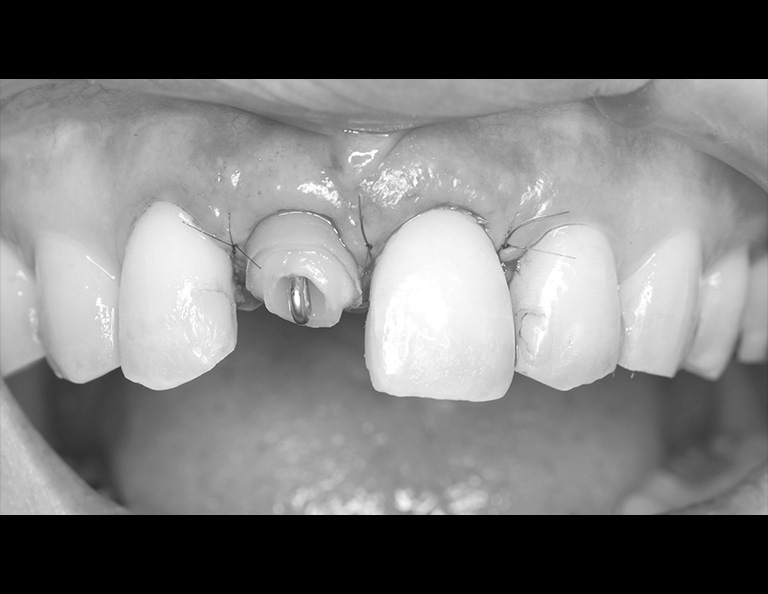

術前の状態です。右上中切歯の被せ物が合っていないことがわかります。また周りの歯の樹脂も劣化が認められます。

被せ物を外すとう蝕が認められました。

土台外すとさらに根管の中にもう蝕が認められました。

残っている歯の量が少ないため、根管治療後に部分矯正にて歯を引っ張り上げる(矯正的挺出)こととしました。

その際は表には仮歯をつけて見た目の確保を行います。

矯正的挺出が終わった状態です。歯とともに歯肉と骨も一緒に引っ張り上げられるので、

手術(歯冠長延長術)によって歯肉と骨を整形し、健康な歯の量を確保します。

歯冠長延長術を行ったところです。

その後土台を築造し、型取りを行います。

右上中切歯にセラミッククラウンを装着して、周りの歯の樹脂もやり替えを行いました。